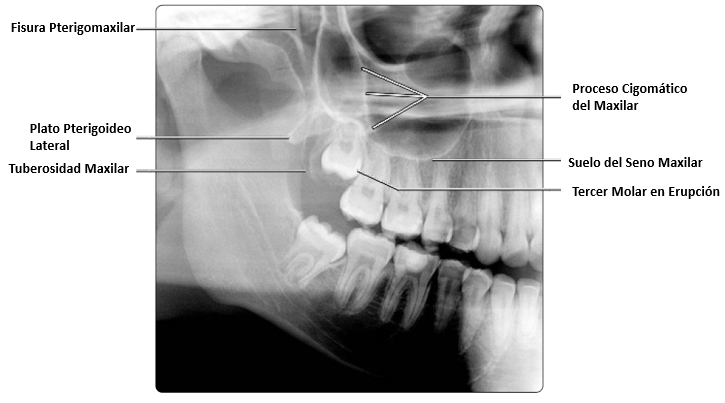

En esta imagen se muestra una vista axial con terceros molares impactados, es importante localizar estructuras anatómicas adyacentes y tomar nota de la proximidad que tienen estos a otros dientes si la extracción está planificada.